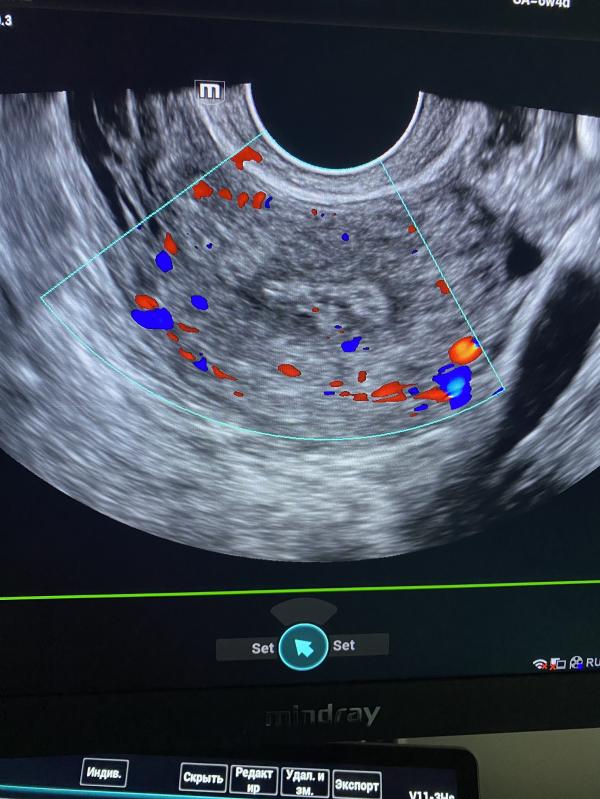

Объясните пожалуйста, вот почему женщина может кровить и ходить на Узи, где ей каждый раз специалист выносит в заключении полип.

Рекомендации : посетить гинеколога, для удаления полипов.